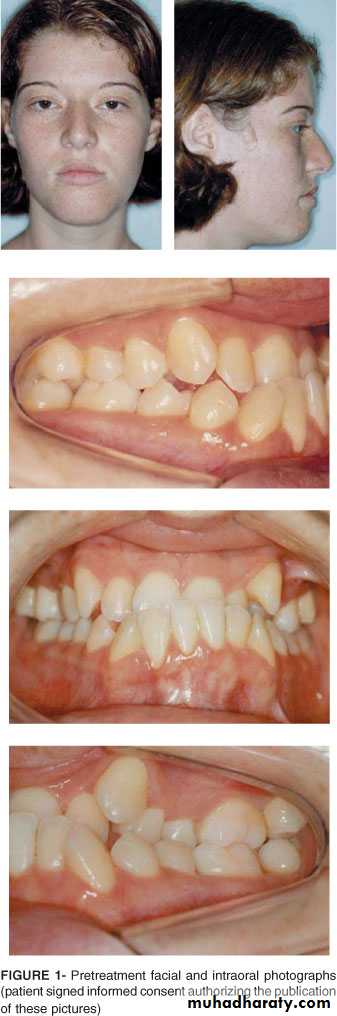

THE MESIOBUCCAL CUSP OF THE LOWER FIRST PERMANENT MOLAOCCLUDES DISTAL TO THE CLASS I POSITION.Condition when class II molar relationship is present with proclined upper central incisors.

There is an increase in overjet.

CLASS II DIVISION 1

Condition when class II molar relationship is present with retroclined upper central incisors, upper lateral incisors may be proclined or normally inclined.

Overjet is usually minimal or may be increased.

CLASS II DIVISION 2